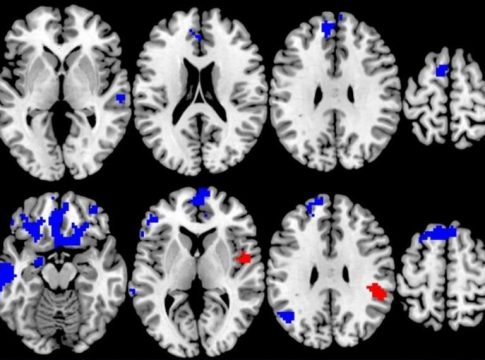

El nuevo estudio, publicado en la revista 'American Journal of Psychiatry', examina los escáneres cerebrales avanzados de 87 adolescentes y adultos con TOC de moderado a severo que fueron asignados al azar a 12 semanas de uno de los dos tipos de terapia.

Pero cuando los investigadores analizaron los escáneres cerebrales realizados antes de que los pacientes comenzaran la terapia y los relacionaron con la respuesta al tratamiento individual, encontraron patrones sorprendentes.

Los escáneres cerebrales se tomaron mientras los pacientes realizaban una simple tarea cognitiva y respondían a una pequeña recompensa monetaria si hacían la tarea correctamente.

Los que empezaron con más activación en los circuitos cerebrales para procesar las demandas cognitivas y la recompensa durante las pruebas tenían más probabilidades de responder a la TCC, pero los que empezaron con menos activación en esas mismas áreas durante las mismas pruebas tenían más probabilidades de responder bien a la TSM.